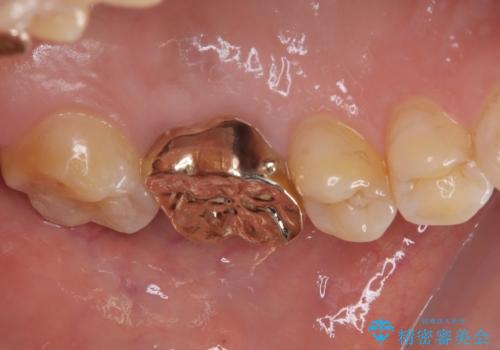

咬み合わせが非常に強く、臼歯のみに咬合力が集中している咬み合わせだったので、根管治療後はPGAクラウン(白金加金合金クラウン)にて補綴する治療計画となりました。

初回の根管治療を終えた2日後には膿の出口が消失し、咬んだときの不快な痛みもなくなりました。

PGAクラウンにしたことで咬み心地に全く違和感がなく、気にされていた審美面も、奥歯でありそれほど目立たないこともありますが、白金加金の色を気に入っていただけたので、患者様には大変満足していただけました。